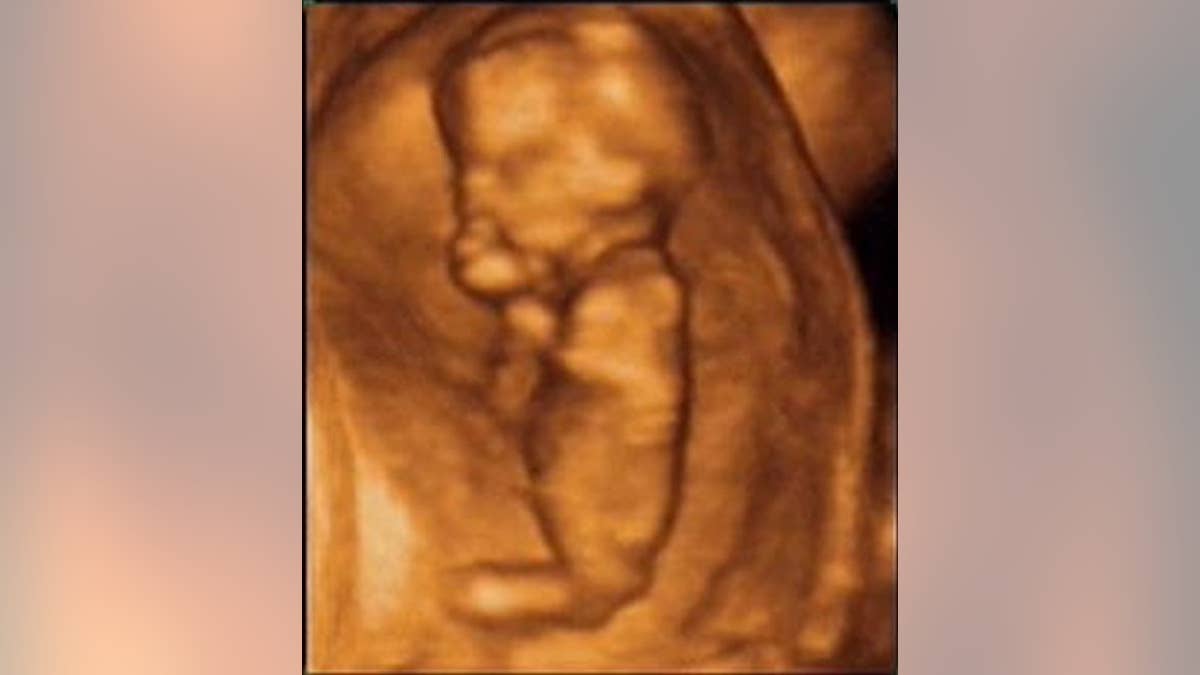

Scientists said ultrasound checks are resulting in some women with perfectly healthy pregnancies wrongly being told that their baby died in the womb. Women then usually would have a termination.

If women experience pain or bleeding during a pregnancy, doctors scan the gestational sac inside the womb. If there is no embryo or the fetus has no heartbeat, they diagnose a miscarriage.

But where there is doubt, doctors are advised to measure the size of the gestational sac seven to 10 days later. If the sac has not grown, a miscarriage is assumed to have occurred.